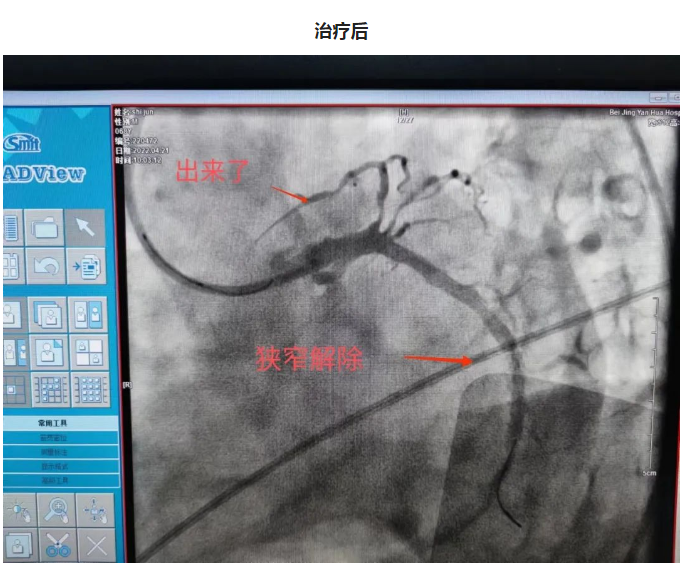

一日凌晨,68岁的石大爷睡眠中突发心前区压榨样疼痛,伴一过性意识丧失,跌倒在地,二便失禁,并胸痛持续不缓解,呼叫120送至我院急诊,心电图提示急性下壁心肌梗死,III度房室传导阻滞,血压74/38mmHg,急诊立即排查新冠肺炎的同时联系我科,秦鹏主治医师立即开通心肌梗死绿色通道,做好防护隔离的同时给予患者静脉溶栓治疗,治疗后患者症状缓解,心电图恢复窦律,抢救成功,后完善冠脉造影提示患者冠脉三支血管病变,右冠状动脉细小,前降支闭塞,回旋支狭窄并可见血栓,李钢主任与患者家属充分交待病情,患者三支血管只剩一支并且是本次心梗的血管,病情危重,需要处理回旋支并尝试开通前降支血管,手术难度及风险较高,患者家属表示理解并要求积极抢救,李刚主任及王志勇、刘丹亮副主任医师给予患者置入IABP(主动脉内球囊反搏)作为保护,反复尝试后给予患者回旋支及前降支闭塞血管进行了治疗,植入冠脉支架,患者转危为安,术后持续IABP辅助,心功能逐渐恢复,抢救成功。